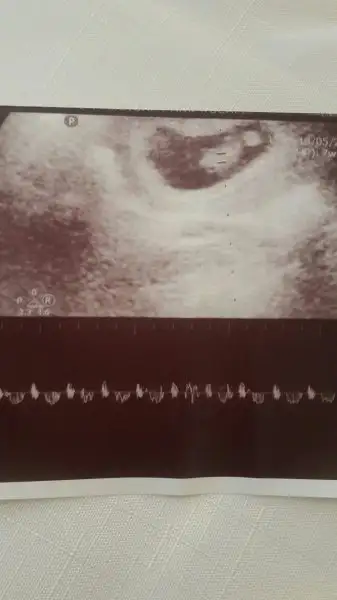

Altaki usg gibiydi benim minnoslarin konumu ve ikiside kiz rabbim saglikla nasip etsin insallah gonlundekiniMerhaba kızlar ilk usg 7+6 aşağıdaki ise bir önceki 6+4 her ikiside karından bana tahminde bulunabilir misinizHavalianne__ yine ben :) Xx

Altaki usg gibiydi benim minnoslarin konumu ve ikiside kiz rabbim saglikla nasip etsin insallah gonlundekini

Merhaba kızlar ilk usg 7+6 aşağıdaki ise bir önceki 6+4 her ikiside karından bana tahminde bulunabilir misinizHavalianne__ yine ben :) Xx